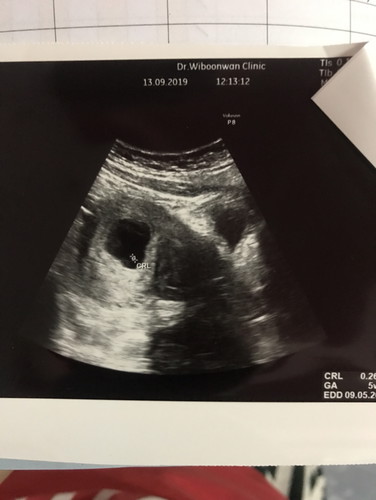

เมื่อวานไปฟังผลเลือดมา คุณหมอบอกว่าเราเสี่ยงสูง 1:169 ต้องส่งตัวเจาะน้ำคร่ำ พอได้ฟังรู้สึกใจสลาย เสียใจมากๆเลยค่ะ ร้องไห้จนไม่มีน้ำตาแล้ว มีแม่ๆคนไหนมีประสบการณ์แบบนี้มั้ยคะ โอกาศที่ผลเจาะน่ำคร่ำออกมาปกติ มีมั้ยคะ 😢😢😢 (เราอายุ24 แฟน31ค่ะ) #16w3d #ผลเลือดเสี่ยงสูง #ดาวน์ซินโดรม #ขอประสงการ์ณแม่ๆหน่อยคะ #ขอบคุณสำหรับคำตอบค่ะ